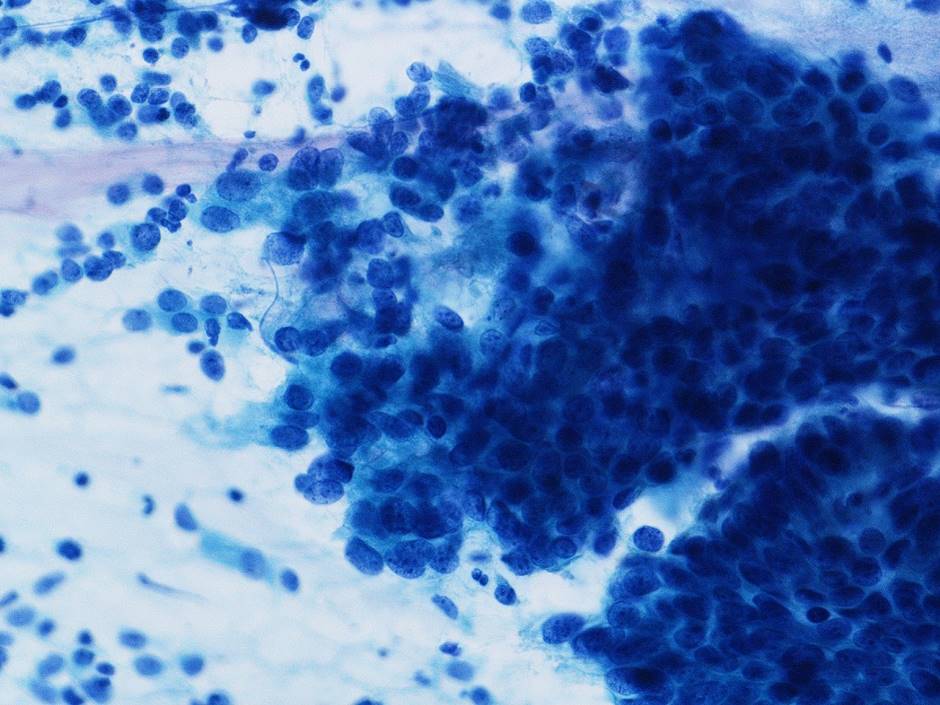

細胞診所見

背景に壊死物質は認められなかった。その中に偏在性核で核クロマチン増量を示す腺系異型細胞の不整形集塊を認めた。柵状配列や腺管構造もみられ上皮内腺癌を疑う細胞と考えた。またN/C比が高く細顆粒状の核クロマチンを有する傍基底型核異常を疑う細胞もみられた

[まとめ] 稀な子宮頸部腫瘍の症例を経験した。細胞診スメア標本では2種類の異なる異型細胞を認識することはできたがLBC標本では難しく神経内分泌癌との推定には至らなかった。腺系病変を疑う症例では、異なる成分の混在を念頭に注意深く鏡検することが重要と考えた。